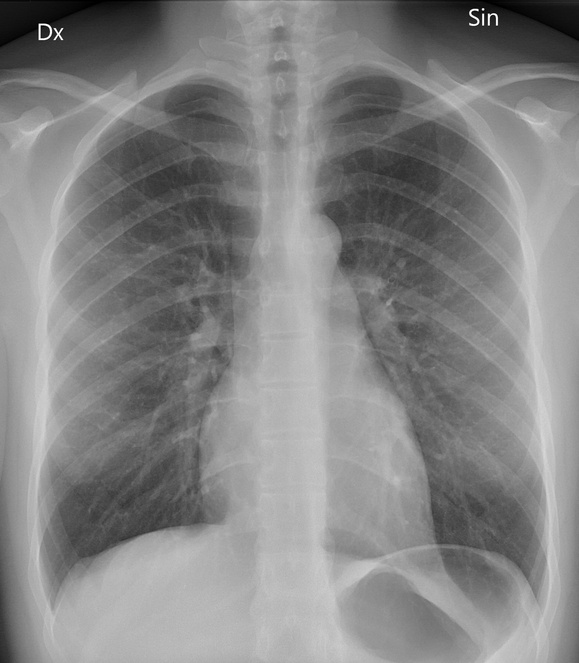

Artificial intelligence in healthcare requires models that are accurate and interpretable. We advance mechanistic interpretability in medical vision by applying Medical Sparse Autoencoders (MedSAEs) to the latent space of MedCLIP, a vision-language model trained on chest radiographs and reports. To quantify interpretability, we propose an evaluation framework that combines correlation metrics, entropy analyzes, and automated neuron naming via the MedGEMMA foundation model. Experiments on the CheXpert dataset show that MedSAE neurons achieve higher monosemanticity and interpretability than raw MedCLIP features. Our findings bridge high-performing medical AI and transparency, offering a scalable step toward clinically reliable representations.